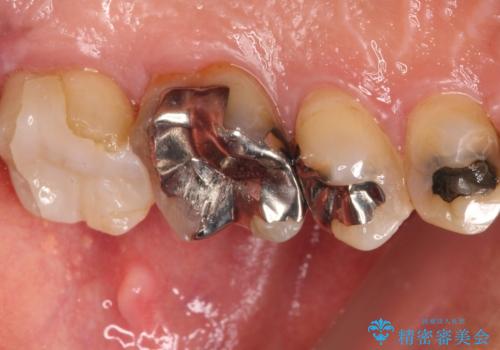

- 奥歯に食べ物がよくはさまるのが気になるとのことで来院された患者様です。

フロスをすると第一大臼歯の部分が引っ掛かり段差になっていることがわかりました。

インレーの範囲が大きいためオールセラミッククランにて補綴することとしました。

前後の歯の詰め物のやり替えも提案しましたが、患者様の希望により第一大臼歯から治療を始めていくこととしました。